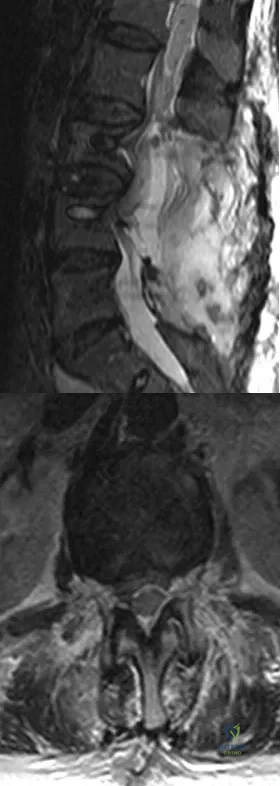

A 78-year-old woman undergoes her third lumbar decompression and fusion from L3 to L5 without complication. On the morning of postoperative day 3, examination reveals painless, flaccid weakness of both lower extremities. She also has an absent bulbocavernous reflex and a mild saddle paresthesia. MRI scans of the lumbar spine are shown in Figures 26a and 26b. What is the most appropriate management at this time?

Explanation